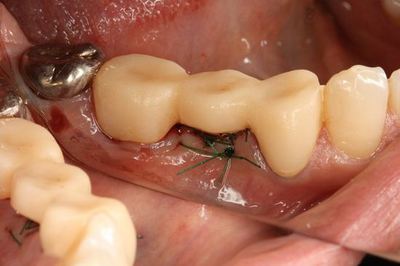

4-0ナイロン縫合糸で縫合しました。

プラスチックの仮歯をセットして治癒を待ちます。